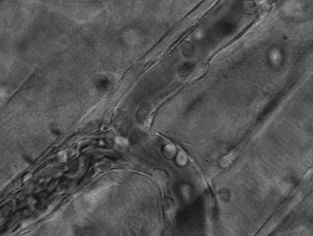

这张动图显示的是嗜酸性粒细胞在趋化作用的“感知”下逐渐聚集到一只秀丽隐杆线虫周围并对它进行攻击的过程。有“成千上万”的嗜酸粒细胞围聚在线虫周围,就像一群蚂蚁,善打“包围战”。